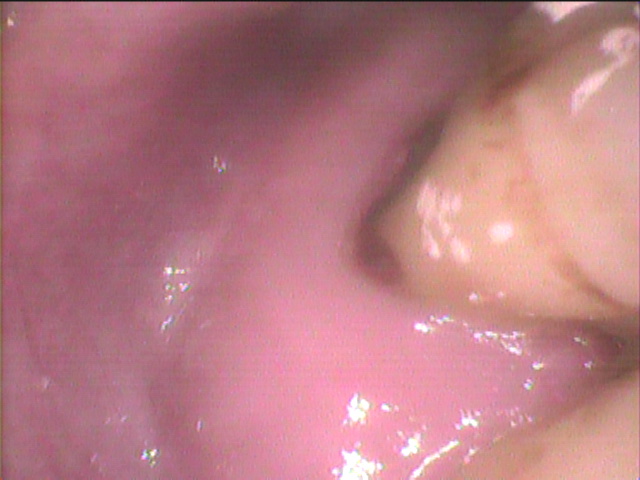

時々しみる程度なら、歯面清掃などの

知覚過敏処置を行うと、緩解する場合が多くあります。

持続的な痛みが出た場合には抜髄して

根管処置にばります。

持続的な痛みがあるので、奥側の歯の髄腔を開けました。

歯根からの虫歯が、神経のある髄腔に達していましたので

神経が変性して、痛みが出たと考えられます。

この後、根管処置をして修復してゆきます。